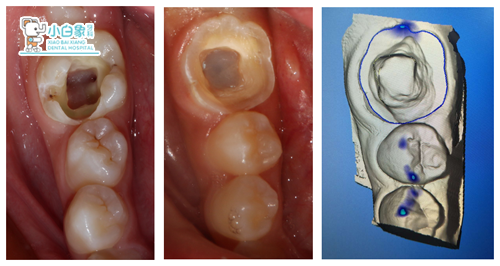

设计过程:

制备牙体,扫像,设计,研磨,上釉,试戴,粘结。